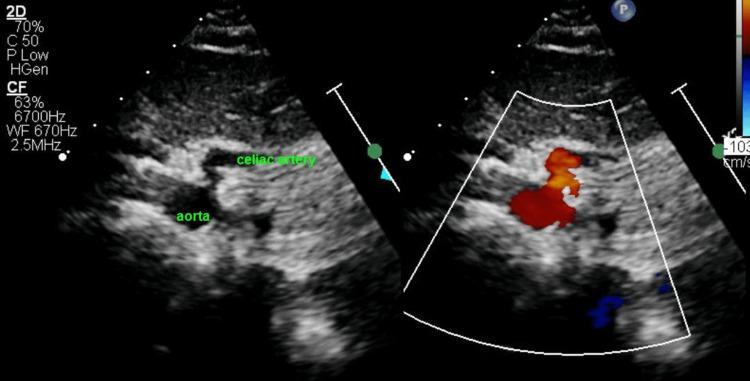

Between 2013 and 2020, there were 82 children, 55 females (67%), mean age 13.9 ± 3.2 years, with MALS and complete record. Mean velocity across the stenotic area was 2.6 ± 0.4 m/s. Forty-six patients (57%) had abdominal pain. Age, gender, weight, body mass index (BMI), and Doppler velocity had no statistically significant influence on symptom occurrence. Conversely, patients with joint hypermobility and symptoms of orthostatic intolerance were more likely to have abdominal pain from MALS. Of 24 patients with joint hypermobility, 18 patients had abdominal pain (p=0.027). Thirty-eight patients with orthostatic intolerance (OI) with MALS complained of abdominal pain vs 13 patients with OI and no abdominal pain (p=<0.0001).

2013年至2020年期间,有82名儿童被诊断为MALS且记录完整,其中55名女性(67%),平均年龄13.9±3.2岁。狭窄区域的平均流速为2.6±0.4米/秒。46名患者(57%)有腹痛症状。年龄、性别、体重、体重指数(BMI)和多普勒流速对症状发生没有统计学上的显著影响。相反,关节活动过度和体位性不耐受症状的患者更有可能因MALS而出现腹痛。在24名关节活动过度的患者中,18名患者有腹痛(p=0.027)。38名患有MALS的体位性不耐受(OI)患者主诉腹痛,而13名患有OI但无腹痛的患者(p<0.0001)。